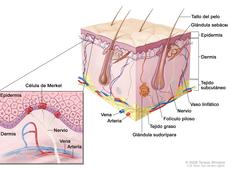

Avelumab, primer tratamiento aprobado para pacientes con carcinoma de células de Merkel

La FDA ha aprobado el primer fármaco hasta ahora para el cáncer poco común de piel, carcinoma de células de Merkel, y datos actualizados muestran un índice mejor de respuesta y que los tumores de pacientes siguieron respondiendo durante por lo menos un año.